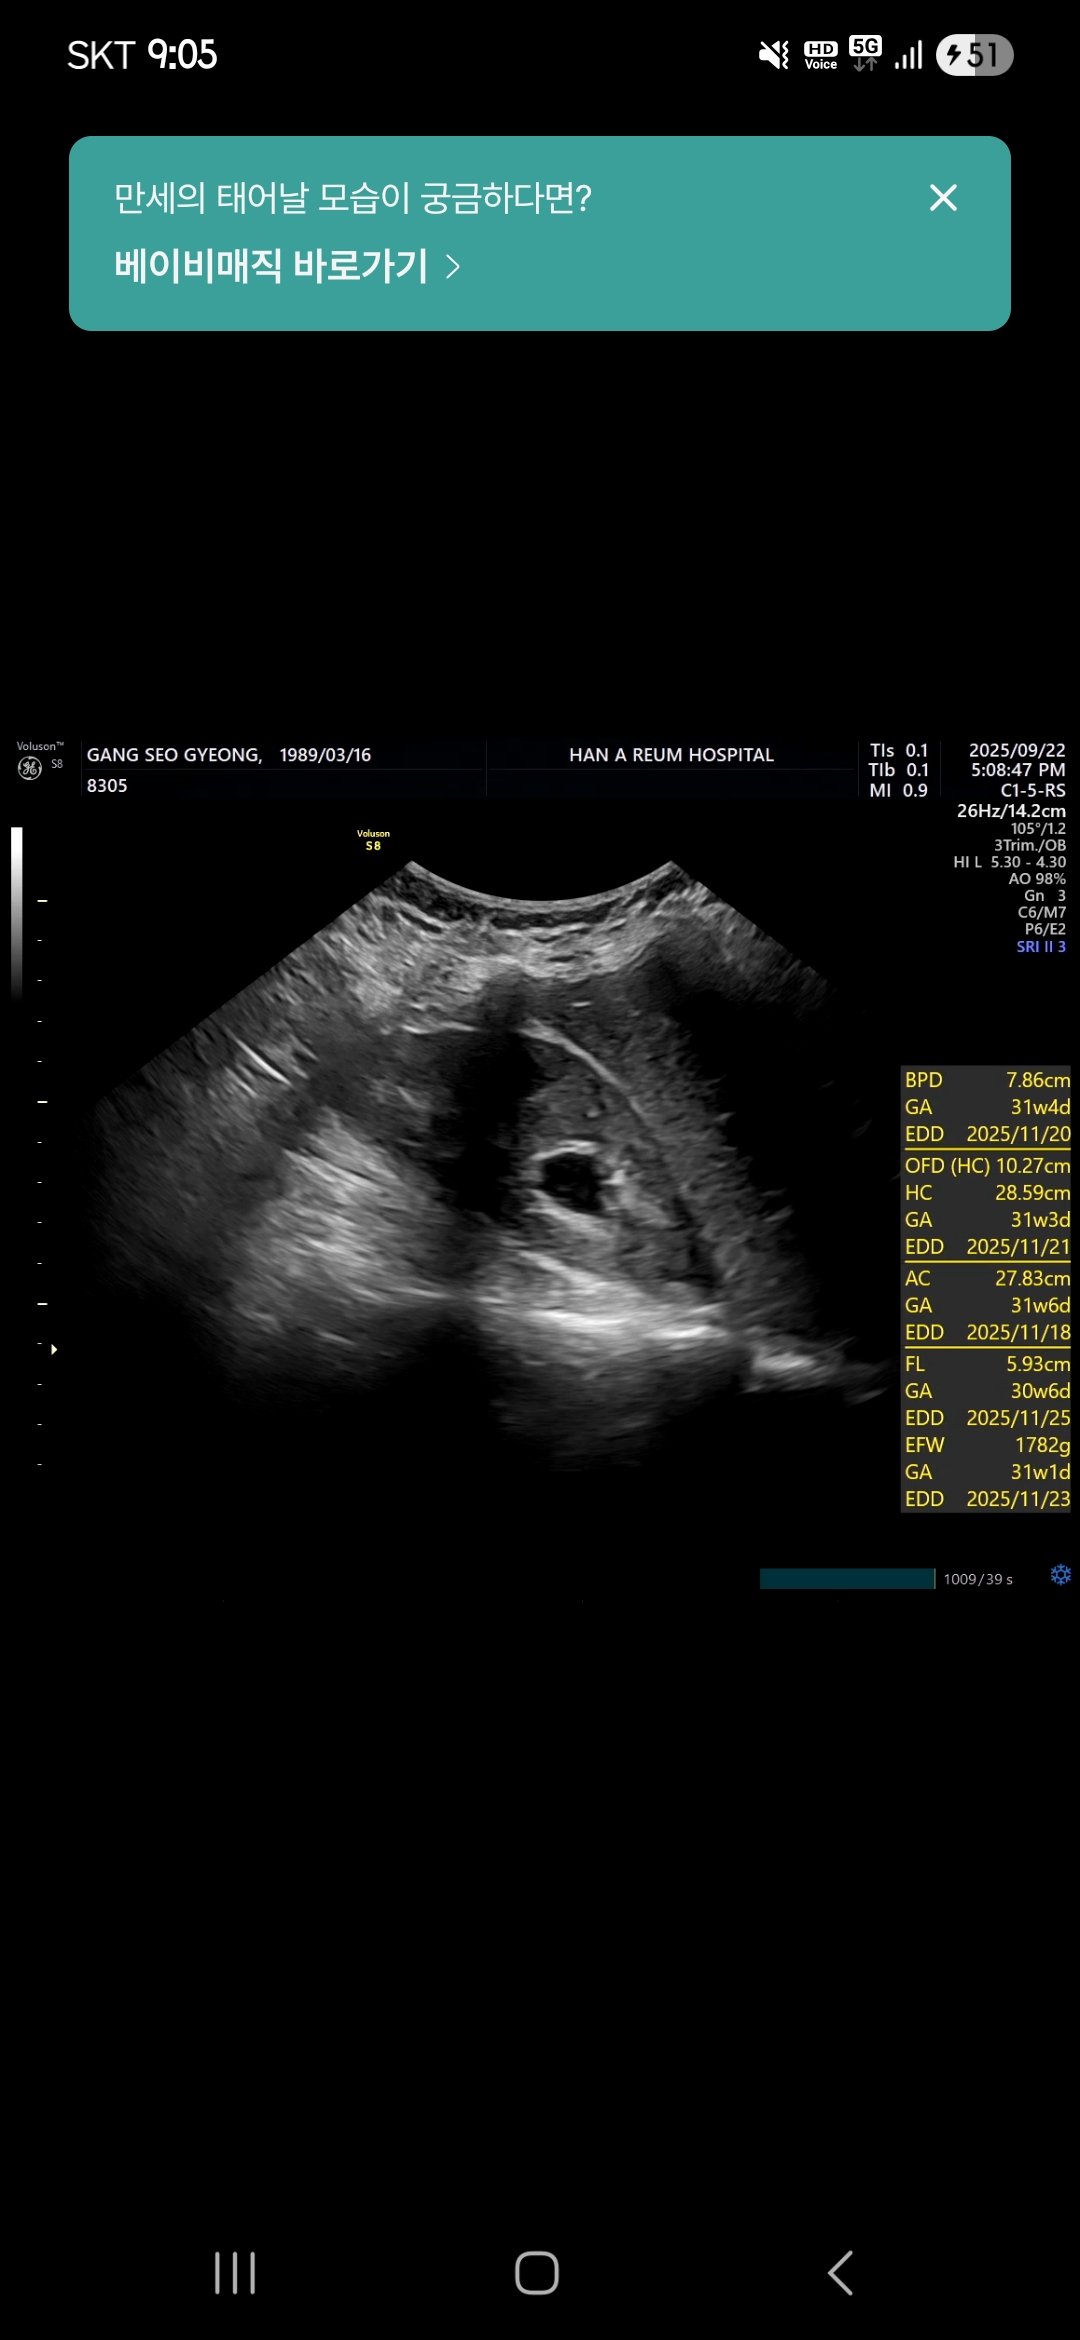

만세 초음파도보고

내 경부길이와 상태도 보고

신장쪽 붓기도 봤다

만세는 잘크고 있고

경부길이는 살짝 열린쪽으로 보면 2.1 길게보면 2.5

짧지만 응급아님

신장붓기는 많이 가라앉았음!